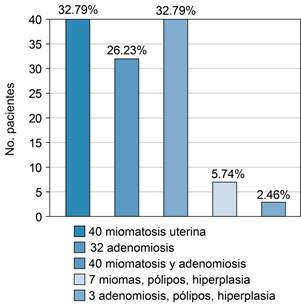

Los datos epidemiológicos sobre adenomiosis no se consideran muy claros, debido a la forma en que se realiza el diagnóstico, se encuentra infradiagnosticado. Su rango de incidencia se tenía contemplado entre 5 y 7%; pero actualmente se estima que puede alcanzar 20 a 35%;3 aunque hay series que señalan que la incidencia de la adenomiosis es de hasta 54% en estudios post mortem. En México, los datos señalan una incidencia de 26.2% o más, dependiendo de la población de estudio (Figura 1).4

Figura 1: Incidencia de adenomiosis en la población de mujeres del ISSEMyM (Instituto de Seguridad Social del Estado de México y Municipios) Satélite entre 2007 y 2010.